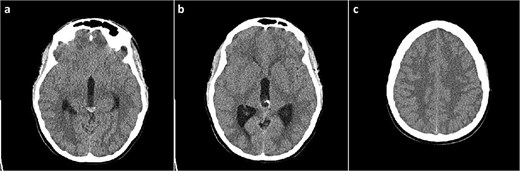

A 19-year-old female patient, with a history of a previously neuroradiologically monitored pineal cyst, presented with complaints of a medically refractory headache with nausea and vomiting. A head computed tomography (CT) scan verified a cystic lesion of the pineal gland with marginal calcifications and hyperdense content in the dorsal part with signs of obstructive hydrocephalus (Fig. 1).

Head CT scan, axial slices. (a) Cystic lesion inside the posterior part of the third ventricle with a hyperdense content in the posterior part of the cyst; (b) probable calcifications in the cyst walls; (c) diffusely obliterated sulci of the convexity as a sign of obstructive hydrocephalus.